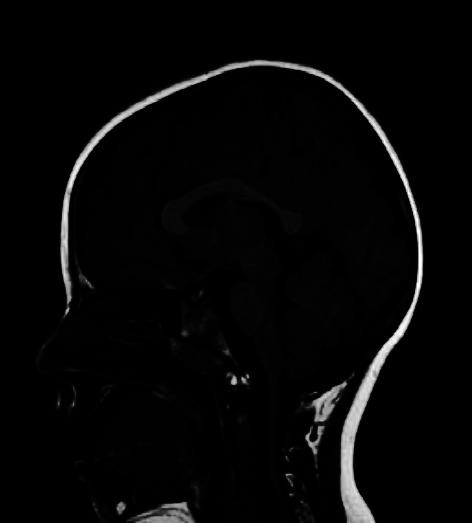

The gene encodes megalin (LRP-2/GP330), a large single-spanning transmembrane glycoprotein that serves as a multiligand endocytotic receptor and mediates the reabsorption of albumin in the proximal renal tubule. is implicated in an autosomal recessive disorder characterized by dimorphisms, ocular anomalies, sensorineural deafness, proteinuria, epilepsy, and intellectual disability: a clinical condition called Donnai-Barrow syndrome (DBS) or facio-oculo-acoustico-renal (FOAR) syndrome. Pathogenic variants in have been reported in fewer than 60 patients, but a detailed description of seizures, electroencephalographic patterns, imaging findings, behavioral phenotype, and long-term follow-up is still needed. We provide a clinical report of two mono-chorionic twins with -related disease manifesting developmental delay, autistic features, seizures, proteinuria, and sleep disorders. By sequencing clinical exome, candidate rare variants, c.6815G > A, p. (Arg2272His), inherited from the mother and c.12725A > G, p. (Asp4242Gly), inherited from the father, were identified. During follow-up, at the age of 7, the main clinical features of the patients included insomnia, autistic features, severe psychomotor delay, and absent speech. The patients were under treatment with risperidone, antiseizure medications (ASMs), and supplementation of alpha-lactalbumin for self-injury and sleep disturbance. Our study confirmed the wide spectrum of behavioral and neurological and psychiatric features of this rare condition, suggesting new treatment options.

该基因编码巨膜蛋白(LRP-2/GP330),这是一种大型单跨膜糖蛋白,作为多配体内吞受体,介导近端肾小管中白蛋白的重吸收。它与一种常染色体隐性疾病有关,其特征为双态性、眼部异常、感音神经性耳聋、蛋白尿、癫痫和智力残疾:一种称为唐纳 - 巴罗综合征(DBS)或面 - 眼 - 耳 - 肾(FOAR)综合征的临床病症。据报道,该基因的致病变异在不到60名患者中出现,但仍需要对癫痫发作、脑电图模式、影像学表现、行为表型和长期随访进行详细描述。我们提供了一份关于一对单绒毛膜双胞胎患有该基因相关疾病的临床报告,其表现为发育迟缓、自闭症特征、癫痫发作、蛋白尿和睡眠障碍。通过对临床外显子组进行测序,鉴定出了两个候选罕见变异,从母亲遗传的c.6815G>A,p.(Arg2272His),以及从父亲遗传的c.12725A>G,p.(Asp4242Gly)。在随访期间,患者7岁时的主要临床特征包括失眠、自闭症特征、严重精神运动发育迟缓以及无语言能力。患者正在接受利培酮、抗癫痫药物(ASMs)治疗,并补充α-乳白蛋白以治疗自残行为和睡眠障碍。我们的研究证实了这种罕见病症广泛的行为、神经和精神特征,提示了新的治疗选择。